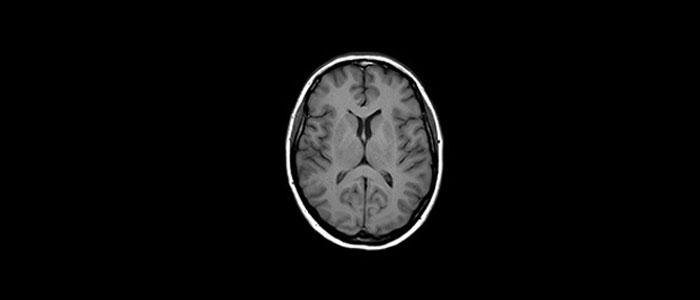

In a society where neurological disorders represent a heavy burden, Philips is committed to provide superb diagnostic clarity and treatment guidance for all patients.